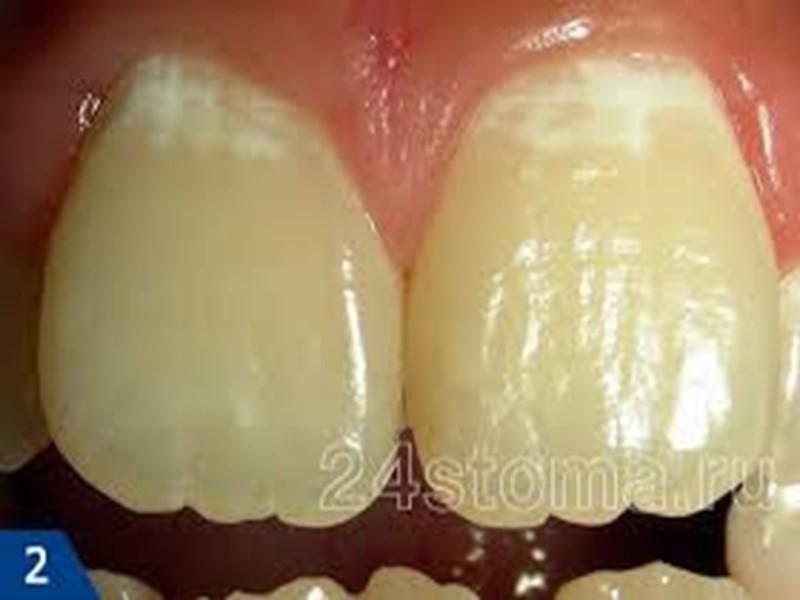

Клинические проявления кариеса зубов Кариес в стадии пятна (macula cariosa). Жалобы на боль, как правило, отсутствуют. В области пятна в отдельных случаях может появиться ощущение повышенной чувствительности к химическим раздражителям (кислое, соленое, сладкое). Если белое или пигментированное пятно расположено на вестибулярной поверхности фронтальной группы, то пациент может предъявлять жалобы эстетического порядка.

Диагностика начального кариеса Объективно: на поверхности эмали видно чаще одиночное меловое или пигментированное пятно диаметром 3-5 мм. Наиболее часто кариозные поражения локализуются в естественных углублениях зуба (фиссурах), контактных поверхностях, в пришеечной области.

Диагностика начального кариеса Для диагностики кариозного пятна предлагается использовать метод высушивания пораженной поверхности эмали. На высушенной поверхности зуба более четко выявляется меловое пятно.

Начальный кариес В очаге деминерализации отмечается снижение содержания кальция, фосфора, фтора и других минеральных веществ. По данным исследователей, потеря кальция в центре очага кариозного поражения достигает 20-30%. С увеличением размера кариозного пятна повышается степень деминерализации эмали.

Начальный кариес Во всех зонах очага деминерализации кристаллы гидроксиапатита претерпевают те или иные изменения: ослабление межкристаллических связей; изменение формы кристаллов и их размеров; уменьшение микротвердости эмали в участке белого и пигментированного пятен, причем микротвердость наружного слоя изменяется меньше, чем подповерхностного.

Начальный кариес В наружном слое эмали изменения выражены меньше, благодаря постоянному процессу реминерализации, а также структурной особенности наружного слоя эмали зуба. Об этом свидетельствуют минимальные изменения микротвердости наружного слоя эмали по сравнению с подповерхностными.